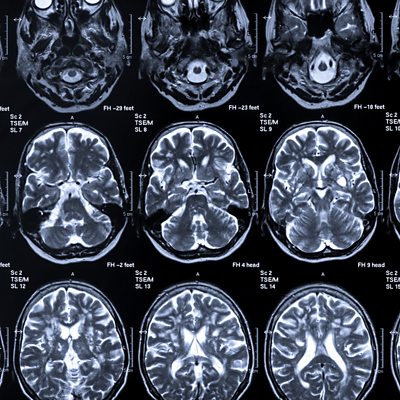

People taking part in scientific studies are not usually told if they are at risk of developing Alzheimer's. And the scientists conducting the studies do not know either. But if better ways are found of detecting early signs of Alzheimer's, should people at risk be told, when there is currently little they can offer to improve the prognosis? Cate Latto, who is taking part in an Alzheimer's Society study called Prevent, because of her family history of Alzheimer's, thinks on balance she would like to know. First broadcast on World at One.